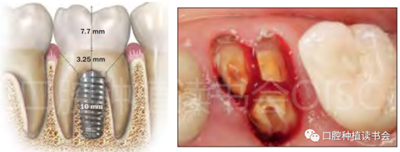

C型拔牙窩,幾乎沒有間隔骨,因此需要種植體與拔牙窩周邊貼合。一般而言,種植體應(yīng)超過根尖至少 3-5 mm,以獲得初期穩(wěn)定性(圖8、圖9),但在后牙位點(diǎn),這樣比較困難;最常見的原因是下牙槽神經(jīng)或上頜竇靠近根尖。

四 后牙區(qū)即刻種植位點(diǎn)的正確三維位置

理想情況下,應(yīng)將種植體的肩臺置于頰舌側(cè)牙槽嵴的根方(1~2 mm)【Fickl等.2008】或者位于牙槽間隔的水平,以補(bǔ)償預(yù)期的牙槽嵴骨重建,并在種植體周圍缺陷中進(jìn)行適當(dāng)?shù)闹补牵▓D10)。

另外,牙根的長度(根分叉到根尖的長度)將決定安全種植的骨高度或深度,應(yīng)避免根尖以外的解剖“危險(xiǎn)區(qū)”(例如,下牙槽神經(jīng)、上頜竇,圖11)。

牙冠和CEJ處的牙齒寬度與種植體平臺的寬度和種植體植入深度有關(guān),因?yàn)檫@個(gè)空間將形成適當(dāng)?shù)拇l輪廓,同時(shí)避免不衛(wèi)生的蓋嵴輪廓。雖然較寬直徑的種植體(6 mm或更寬)可以為適當(dāng)?shù)难拦诖l輪廓提供一個(gè)可預(yù)測的平臺,但如果將種植體放置在適當(dāng)?shù)拇怪蔽恢茫褂脴?biāo)準(zhǔn)直徑(4-5 mm)的種植體也可以獲得好的穿齦輪廓。